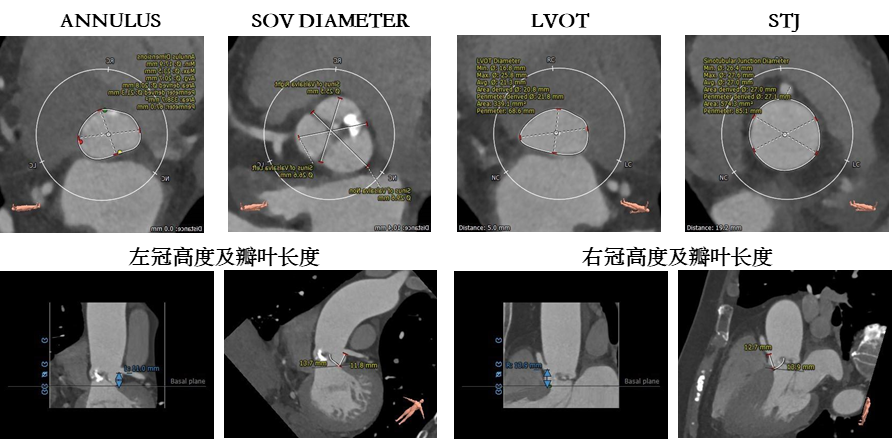

1.主动脉瓣瓣环周长67.0mm,平均周长径20.7mm。

2.主动脉瓣呈Type 1型二叶瓣,瓣叶纤维增厚,中度钙化,钙化散在分布。

3.左冠开口较低,左冠瓣长度大于冠脉开口至瓣叶附着缘距离,瓦氏窦内径偏小,有一定冠脉遮挡风险。

4. 主动脉瓣环与水平面夹角可,主动脉弓角度与宽度可。入路血管局限少量钙化,双侧血管内径良好,整体入路血管条件尚可。

1.瓣叶纤维化增厚严重,瓦氏窦偏小,左冠瓣长度大于冠脉开口至瓣叶附着缘距离,左侧冠脉堵塞风险很高。

2.该病例少量钙化,合并主动脉瓣少量反流,瓣膜锚定难度偏高,有瓣膜位移风险。需采用较高位(瓣环下0-2mm)释放策略,释放位置需精准。

1.该病例主动脉瓣瓣环平均径、周长径数值位于瓣膜推荐型号AV23型号,球囊使用18mm进行预扩,需综合考虑左侧冠脉阻塞风险和瓣膜位移风险,术中需通过主动脉根部造影和球囊预扩最终确定瓣膜尺寸。